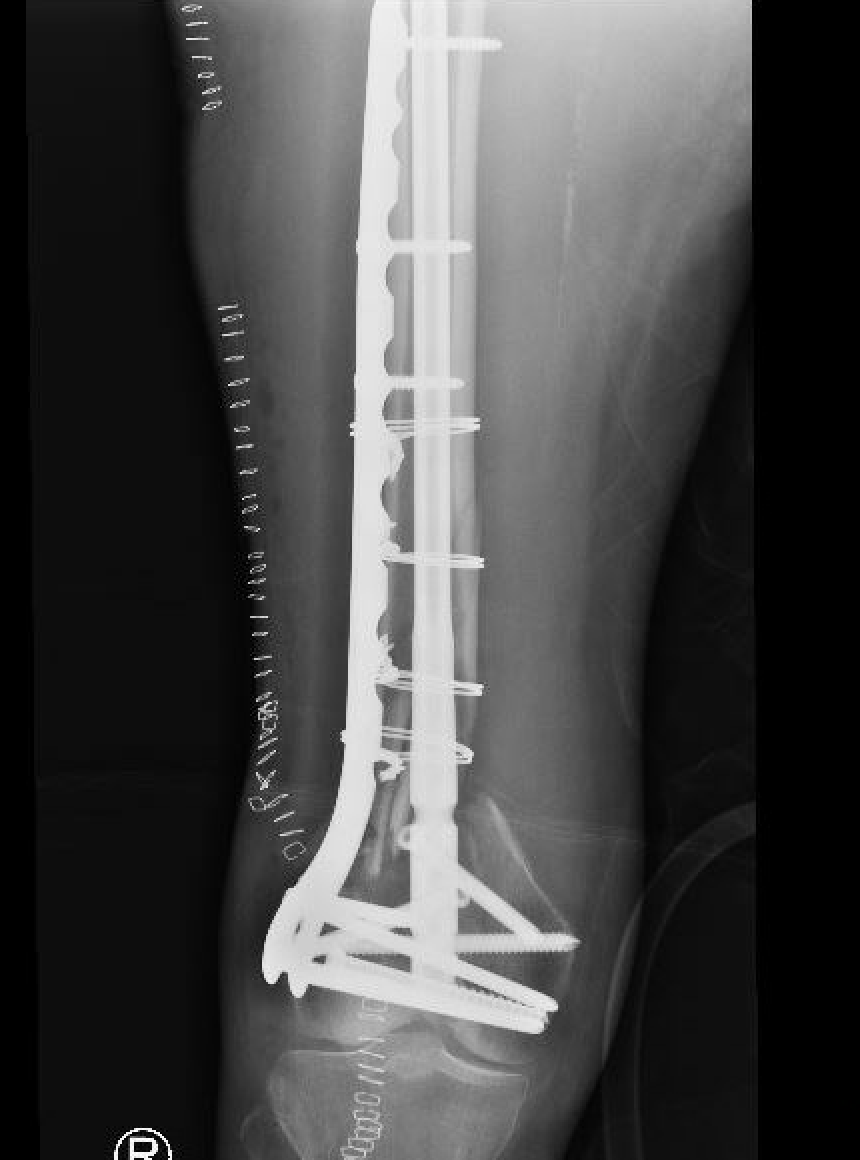

Type C: Complete articular

Xray / CT

Options

Dual Plate

Plate + Retrograde nail

Indications

Significant comminution

Loss of medial cortical buttress